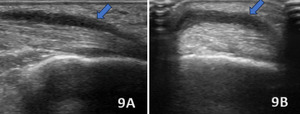

ACHILLES PERITENDONITIS

Figures 8A (LAX View) and 8B (SAX View):

Ultrasound findings of Achilles peritendonitis include a hypoechoic crescent (blue arrows) abutting the posterior surface of the distal Achilles tendon, with increased vascularity on Doppler imaging in the peritendinous region and Kager’s fat pad, without increased echogenicity. The Achilles tendon itself appears intact, with no signs of tendinosis. These findings differentiate peritendonitis, which affects the tissues surrounding the tendon, from tendonitis, which involves intrinsic changes within the tendon structure.